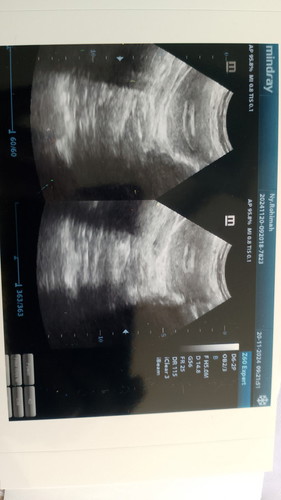

Assalamualaikum Bismillah MasyaAllah tabarakallah. Rasa nya sedih bgt.. bawaannya tiap HR nangis.. mencoba ditahan dg perasaan2 campur aduk JD 1 tp nyata nya TDK bisa..air mata yg selalu jatuh berlinang dg sendirinya. Mencoba sabar n ikhlas tp nyatanya tangisan ini TK bisa paksa henti. 2xkeguguran tanpa indikasi.. Kehamilan ke 1&ke3. Ternyata TDK bisa kecapean bgt. Bingung dg ekonomi pas2an. Pengin priksa RS lagi dg dr yg bagus terkendala biaya. Hanya bisa lewat klinik..dan hasil yg kurang memuaskan dihati. Pengen bikin BPJS ternyata TDK bisa Krn sy SDH termasuk peserta PBI tp statusnya non aktif. Saya perantau..dg pendapat dagang pas2an kadang dpt kadang TDK. Mohon Do a. Nya semoga Rahim saya nnti bisa bersih pasca keguguran..tanpa hrs kuret. Jujur saya takut di kuret N biayanya pasti TDK sedikit. SDH berkali2 priksa USG.. USG terakhir seperti ini gambarnya masih ada sisa.. klinik y ditanya Kya gimana gitu.. kurang puas dengan jwb y. Suruh balik lg klo SDH seminggu biar di USG lg kta y.. Saya JD TDK ada selera mkn dll. Saya berharap semoga rahim saya bisa bersih dr sisa2 trsbt..biar GK usah bolak balik priksa .cape dll.Krn faktor ekonomi juga . Sekali priksa ke klinik biasa 280ribu Kemaren di RS 1juta lebih. Bagi kami itu mahal yg ekonomi y pas2an. Pengin priksa di RS langganan.yg dr bagus..jauh bgt.. SDH TDK baik2 saja ekonomi y.&posisi kami TDK punya kendaraan pribadi. Byk yg nyaranin KB.. mengingat ekonomi kami yg pas2an . Suami slalu bilang kalau masalah rejeki mah SDH ada yg ngatur ada saja pasti jln y...suami slalu menguatkan untuk TDK pernah takut..tp klo SDH begini sy yg slalu JD kepikiran. Krn perempuan &laki2 beda pemikiran y. Kalau perempuan mah masalah apa aja dipikirin. Saya pengen pulih dulu dr pasca keguguran..dan sebelum rahim q benar2 bersih saya selalu kepikiran.. gimana nantinya.. Takut knp2. Jujur dlm pikiran n hati q ada keinginan pengen hamil lg suatu saat nanti. Tp ada pikiran yg mengganjal..kalau SDH begini JD punya perasaan takut.. perasaan2& pikiran apa saja macem2. Saya berharap suatu saat nanti ekonomi keluarga ku stabil baik2 saja..bertambah banyak Saya berharap suatu saat nanti bisa hamil lg dg kehamilan yg sehat..kuat..normal..nyaman. ##Sharing_dong_Bund #bantujawab #ingintahu